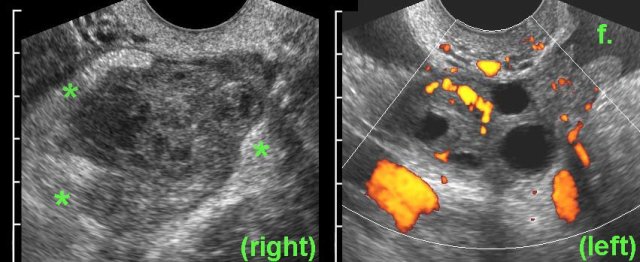

case 1

Ill,

young woman with RLQ pain and a CRP of 160.

TVUS shows a hyperemic,

swollen right ovary, with irregularly defined, thick-walled follicles, filled

with debris-like material (pus), surrounded by hyperechoic fat (*).

PCR was positive for Chlamydia the next day.